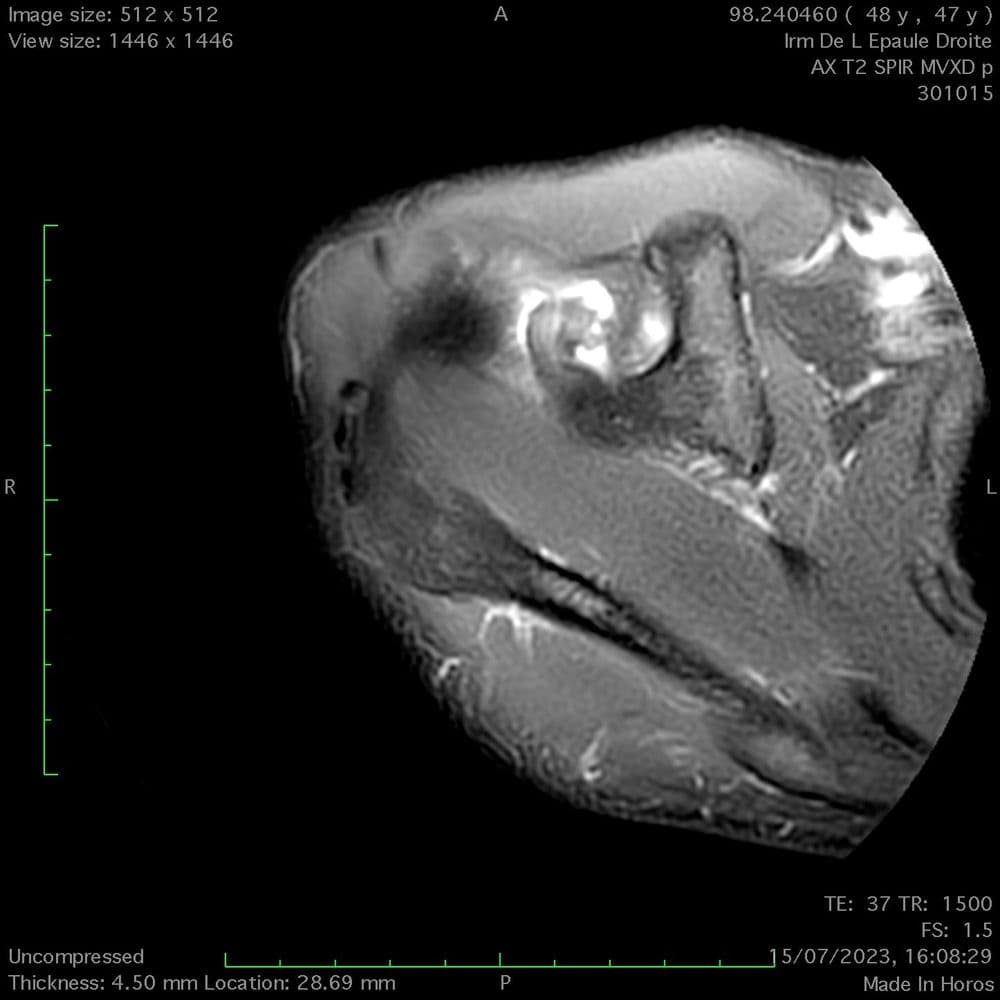

Lésion myotendineuse 1b (BAMIC) du sous scapulaire chez une basketteuse

MRI